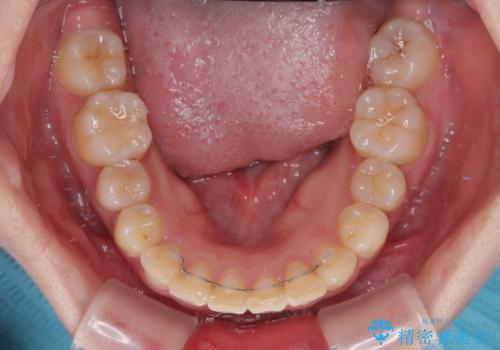

マウスピース矯正は、自己管理が非常に重要と事前にお伝えしておりましたが、毎日のマウスピース装着が遵守できず、ワイヤー装置での矯正治療へ変更することとなりました。

インビザラインからワイヤー装置へ変更すると、費用が追加となるため、ワイヤー装置は目立つものの費用を抑えることのできるメタルブラケットを使用しました。